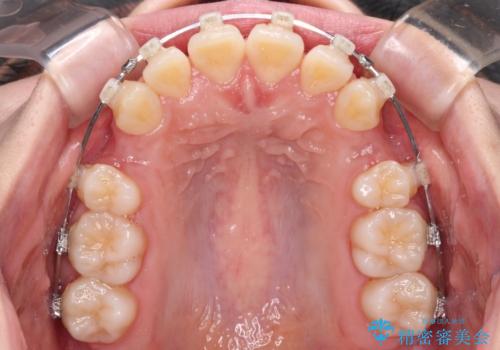

- クリアブラケット

- 3年9ヶ月

- 30回以上

深い咬み合わせの改善に時間がかかりましたが、下顎前歯がしっかりと見えるまでに整えることができ、口元の突出感も大幅に改善することができました。